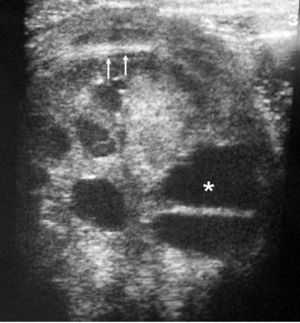

El tumor rabdoide se presentó en un niño de 5 meses estudiado por masa abdominal palpable y hematuria, con el antecedente de un hermano gemelo fallecido poco tiempo antes por tumor cerebral. El estudio con ecografía y TC abdominal demostró una masa renal sólida, heterogénea e hipodensa con poco realce. Se completó el estudio con ecografía transfontanelar y TC craneal identificando una masa cerebral sincrónica, intraaxial, frontal paramedial, sólido-quística con calcificaciones (fig. 7). No se conoció la histología del tumor cerebral por seguimiento del paciente en otro centro.

Fig. 7 Tumor rabdoide. Niño de 5 meses con hematuria y masa abdominal. (A) Ecografía abdominal. Corte longitudinal renal izquierdo. Masa sólida, heterogénea (M), bien delimitada en polo inferior de riñón izquierdo. (B) Tomografía computarizada abdominal con contraste intravenoso. Masa renal hipodensa, de aspecto infiltrativo, con crecimiento extrarrenal y tenue captación de contraste. (C) Tomografía computarizada craneal. Masa intraaxial, sólido-quística, fronto-temporal derecha, que desplaza la línea media, con un área de calcificación periférica.

Supone el 2-3% de todas las masas renales en la edad pediátrica y es el tumor renal de peor pronóstico1,4. Aproximadamente el 80% tiene lugar en menores de 2 años y el 60% en menores de 1 año, siendo muy infrecuente en mayores de 5 años14.

Puede presentarse con hematuria o hipercalcemia paraneoplásica, por elevación de niveles de parathormona, pero debido a su agresividad es frecuente que se muestre con los síntomas derivados de las metástasis. Se asocia a la aparición sincrónica o metacrónica de un tumor cerebral primario, generalmente en la línea media y frecuentemente en la fosa posterior, que puede tratarse de un tumor neuroectodérmico primitivo, ependimoma, astrocitoma del troncoencéfalo o cerebeloso o meduloblastoma4,14,15.

El paciente que presentamos se estudió por hematuria y masa abdominal palpable a los 5 meses de edad. En el momento del diagnóstico se encontró una masa renal y una masa cerebral en el lóbulo frontal.

Histológicamente está compuesto por células que recuerdan a las de los tumores musculoesqueléticos. Macroscópicamente es una masa que suele crecer del parénquima perihiliar, infiltrando la médula, el seno renal y el sistema colector. Al diagnóstico suele ser grande e invadir todo el parénquima renal14. Los estudios de imagen muestran una gran masa lobulada, heterogénea, con áreas de necrosis y hemorragia y, en ocasiones, con calcificaciones lineales. Es característica, aunque no patognomónica, la existencia de una colección líquida subcapsular periférica, que puede representar un hematoma o bien restos tumorales necrosados14-16. La existencia de esta colección, junto a la hipercalcemia y el rango de edad, son hallazgos característicos que comparte este tumor con el nefroma mesoblástico. Sin embargo, dada la baja frecuencia de estos tumores, ante una colección líquida periférica en un niño pequeño con masa renal, el diagnóstico diferencial más probable será el de nefroma mesoblástico5,15. En nuestra serie de los 11 nefromas mesoblásticos encontrados 7 (63,3%) tenían una colección líquida subcapsular, mientras que el único caso de tumor rabdoide se presentó como una masa intrarrenal sin colección periférica.